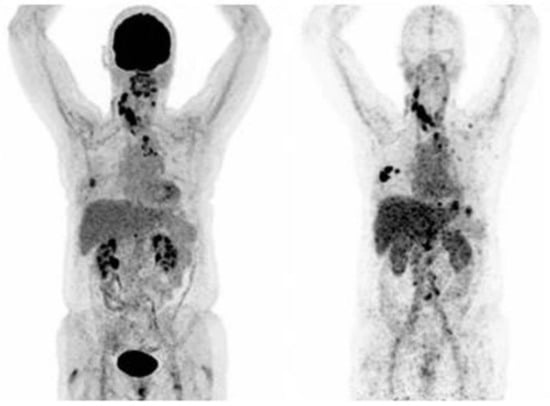

- Ballal, S.; Yadav, M.P.; Kramer, V.; Moon, E.S.; Roesch, F.; Tripathi, M.; Mallick, S.; ArunRaj, S.T.; Bal, C. A theranostic approach of [68 Ga] Ga-DOTA. SA. FAPi PET/CT-guided [177 Lu] Lu-DOTA. SA. FAPi radionuclide therapy in an end-stage breast cancer patient: New frontier in targeted radionuclide therapy. Eur. J. Nucl. Med. Mol. Imaging 2020, 1–3. [Google Scholar] [CrossRef]